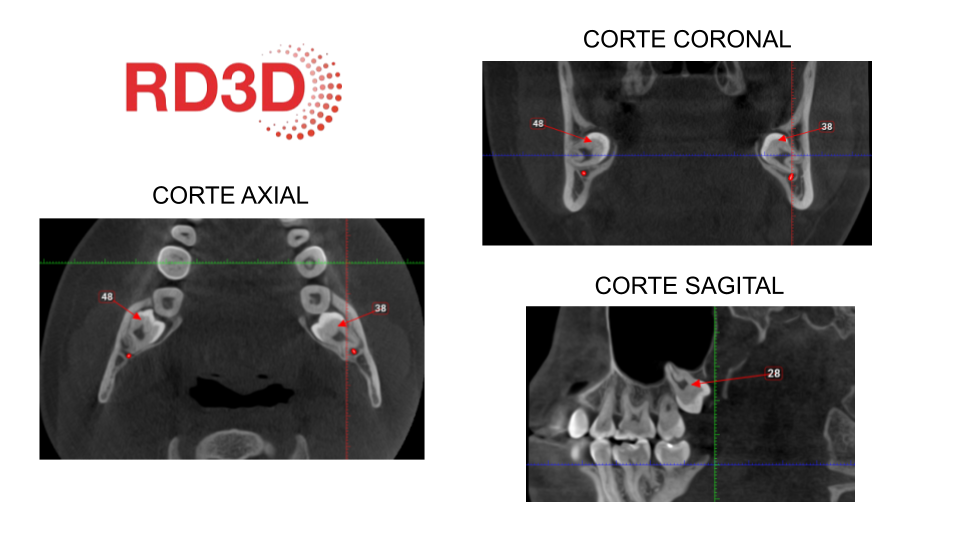

En casos más complejos, el CBCT (tomografía 3D) ofrece imágenes de alta definición, indispensables para valorar la cercanía de las raíces a estructuras nerviosas y reducir riesgos durante la cirugía.

*En la imagen realizada en RD3D observamos los diferentes planos o cortes de un CBCT en el que se señalan las muelas del juicio con su respectivo número de pieza.